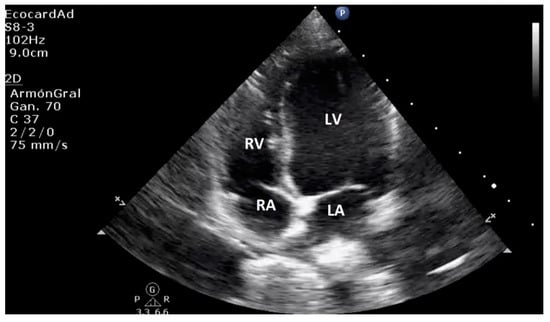

4.3. Canine Myxomatous Mitral Valve Disease. Comparative Transthoracic Echocardiography with Human Mitral Valve Prolapse

| Normal Basic Echocardiographic Views | Human: Parasternal long axis, parasternal short axis, apical four chamber, apical four-chamber view, subxiphoid (subcostal), suprasternal view, and IVC views. Canines: Four-chamber right-sided parasternal long-axis view, five-chamber right-sided parasternal long-axis view, right-sided short-axis view of the left ventricle at the level of the papillary muscles, right-sided short-axis view at the level of the left atrium and aorta. |